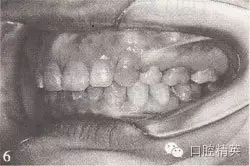

參見圖9-33 雙側(cè)后牙鎖頜矯治前后

A.雙側(cè)后牙鎖頜矯治前